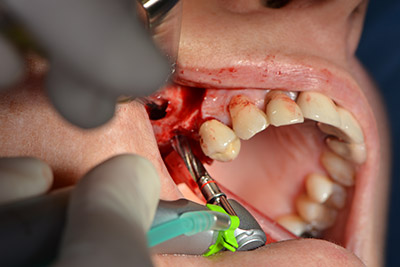

Im nächsten Schritt wird die Sinusbodenelevation mit simultaner Implantation durchgeführt. Für die bukkale Fensterung der Kieferhöhlenwand gibt es auch hier bei der Implantmed an der ersten Position eine Voreinstellung.

Mit 35.000/min wird das Fenster angelegt und anschließend die Schneidersche Membran nach kranial präpariert. (Abb. 13 bis 14).

Präparieren der Schneiderschen Membran